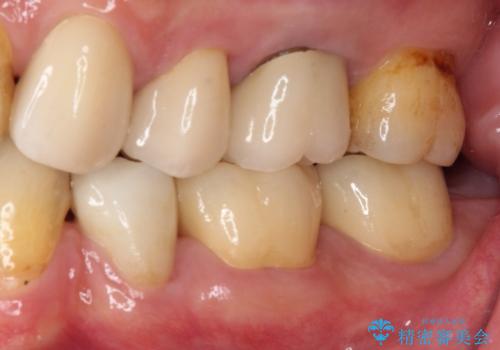

虫歯を取り除き、仮歯を装着した時点でしみる感覚は改善されました。

オールセラミッククラウン装着後も経過は良好です。